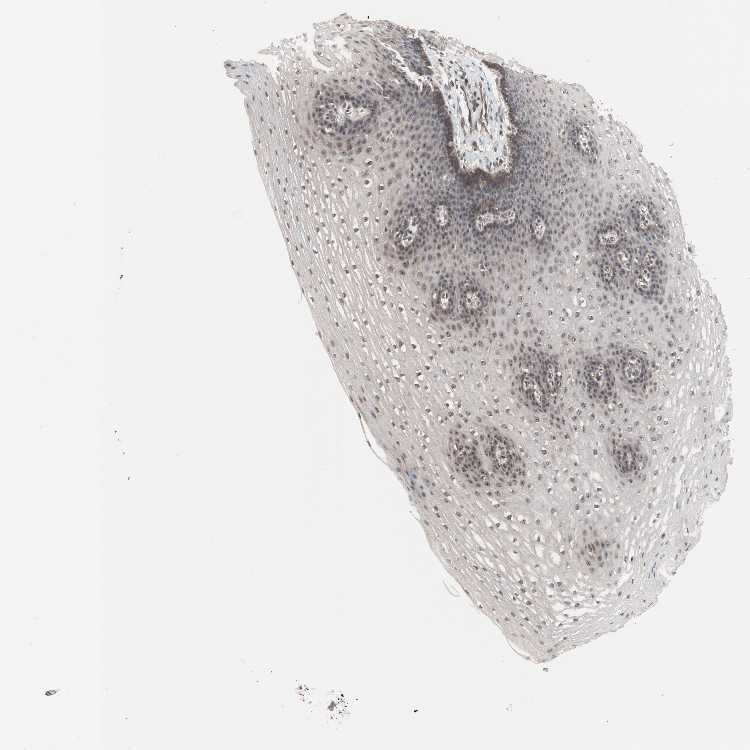

ESOPHAGUS - Antibody stainingi

Antibody staining in the annotated cell types in the current human tissue is reported as not detected, low, medium, or high, based on conventional immunohistochemistry profiling in selected tissues. This score is based on the combination of the staining intensity and fraction of stained cells.

Each image is clickable and will lead to virtual microscopy that enables deeper exploration of all samples and also displays staining intensity scores, fraction scores and subcellular localization as well as patient and tissue information for each sample.

Antibody CAB005261

Squamous epithelial cells Low